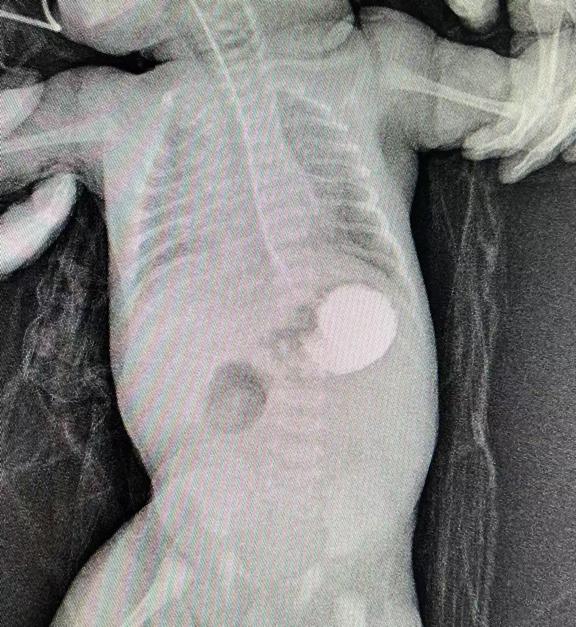

圖片7.jpg

術(shù)前造影提示十二指腸遠端閉鎖